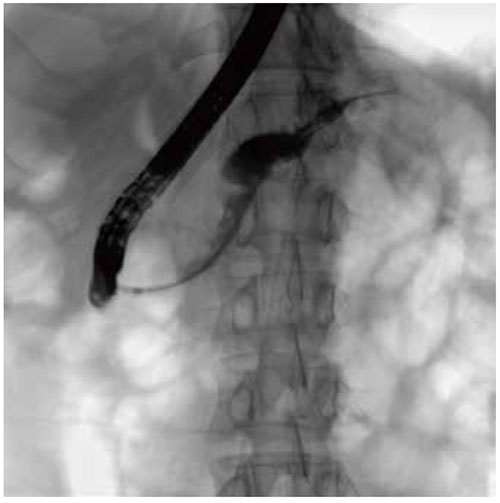

Versatile functions designed for intervention:

• Adjustable SID: The FPD can be lifted in a wide range to flexibly adjust SID and be close to the examination area for clearer fluoroscopic images.

• High-pressure injector interface:When fluoroscopy is started, the high-pressure injector automatically injects the contrast agent, which simplifies the doctor’s workflow and obtains high-quality angiography

images in a short time.

• DSA: DSA is used to clearly visualize blood vessels in a

bony or dense soft tissue environment. Images are produced using contrast medium by subtracting a “pre-contrast image” or mask image from subsequent images, once the contrast medium has been introduced into a structure.